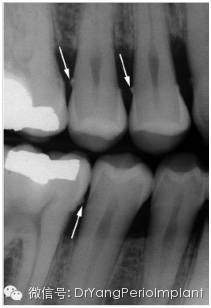

垂直咬翼片更适合牙周检查,为什么呢?你想啊,牙周病患者通常有骨吸收,如果吸收严重,水平咬翼片可能没法显示牙槽脊啊!另外,因为咬翼片在口腔里置放的位置,它引起的图像变形是最少的。当然,它的不足之处是无法显示根尖。这不,全口X光检查包括根尖片和咬翼片,为的是取长补短。

水平咬翼片,对有严重骨吸收的患者,牙槽脊就看不见了X光片取自笔者治疗过的病人)。

垂直咬翼片,清晰显示牙槽脊位置(图片取自Carranza Clinical Periodontology 201211版)